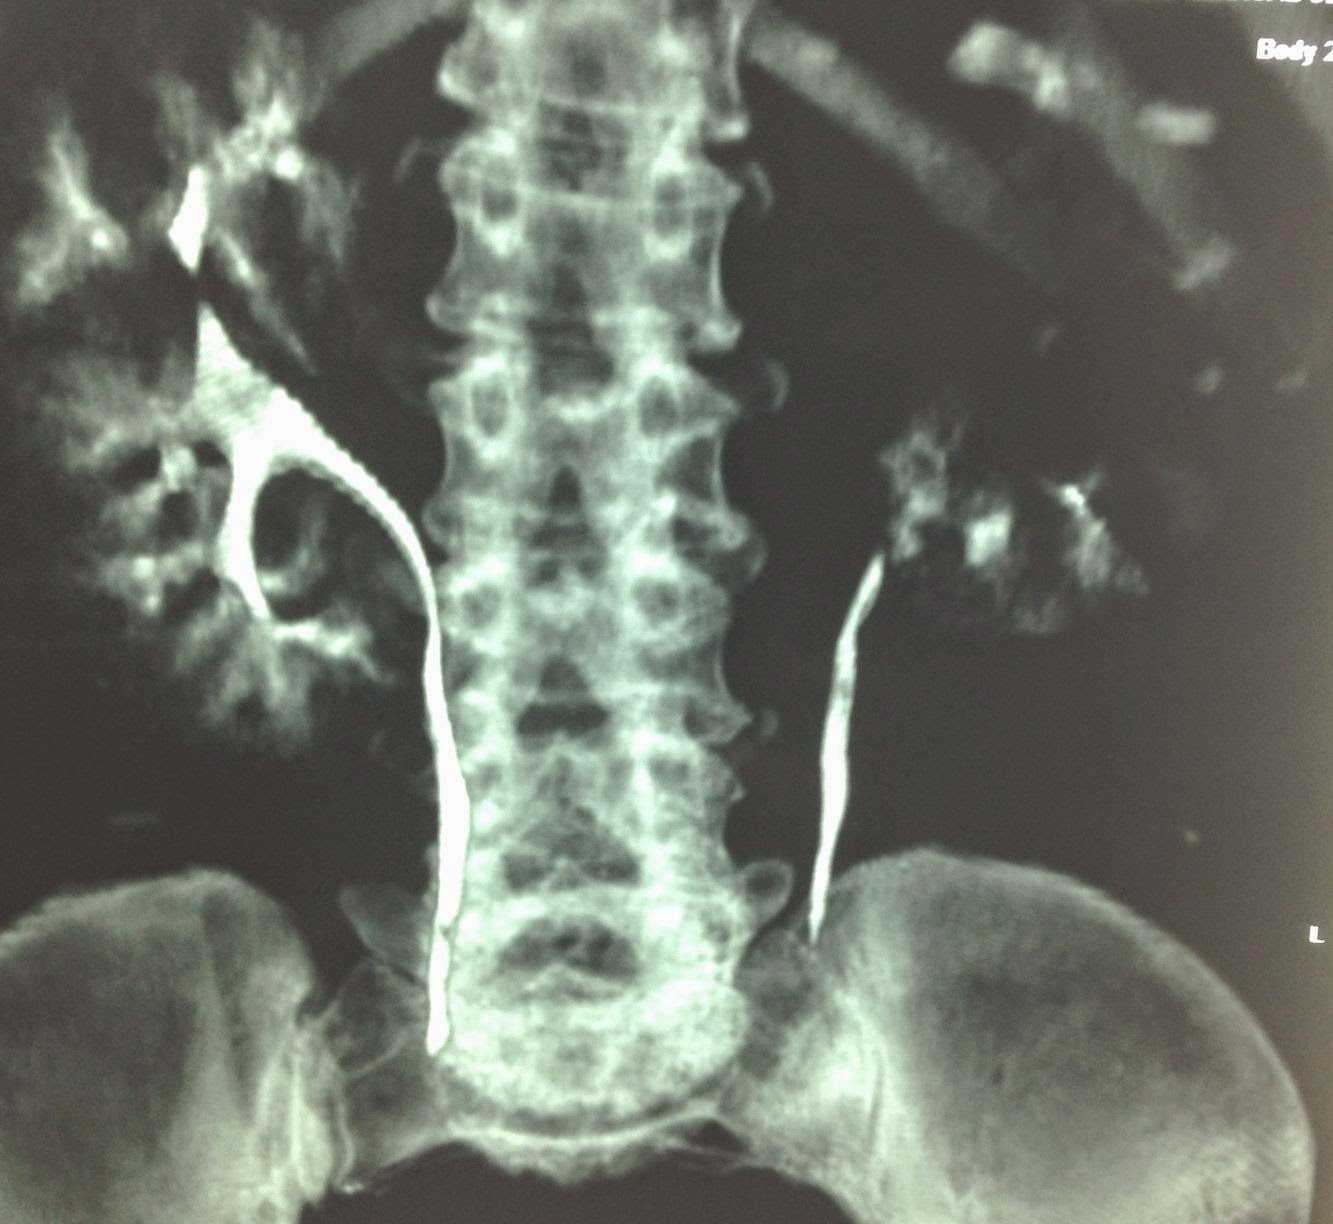

Renal abscess with perinephric extension Radiology Cases

From radiologycases.my

Renal abscess with perinephric extension Radiology Cases Abscess Kidney a renal abscess is a pocket of infection in the kidney that can cause fever, pain, and kidney damage. a kidney infection (pyelonephritis) is a serious bacterial infection that can cause fever, pain and kidney damage. renal and perinephric abscesses are rare but very severe conditions resulting from infections in or. a perinephric abscess is a. Abscess Kidney.